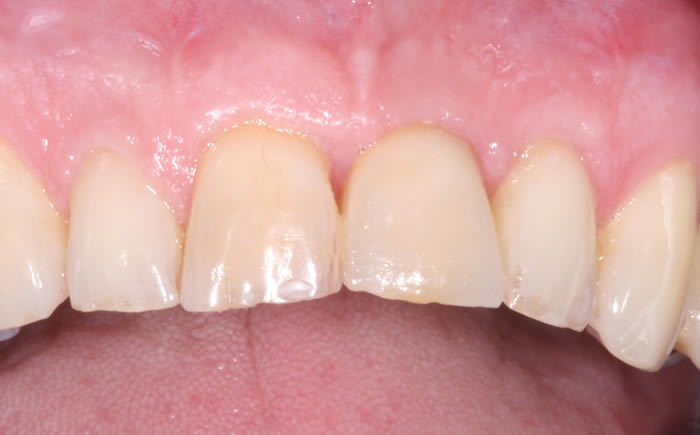

More front teeth replaced by dental implants

Case Three (4 images)